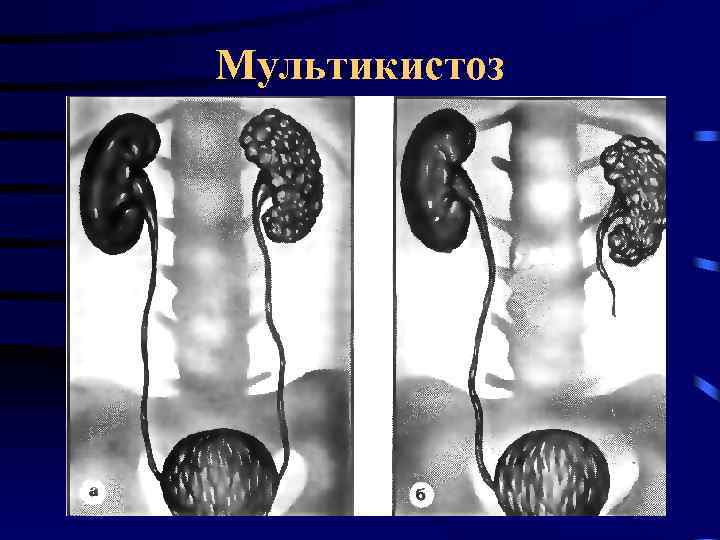

Кистозные аномалии почек Мультикистоз • • Односторонняя, Результат дисэмбриогенеза Мочеточник отсутствует или атрезия Дисплазия паренхимы, возможны неопластические изменения (Dimmick et al. 1989)

Кистозные аномалии почек Мультикистоз • • Односторонняя, Результат дисэмбриогенеза Мочеточник отсутствует или атрезия Дисплазия паренхимы, возможны неопластические изменения (Dimmick et al. 1989)

Мультикистоз

Мультикистоз

Мультикистоз

Мультикистоз